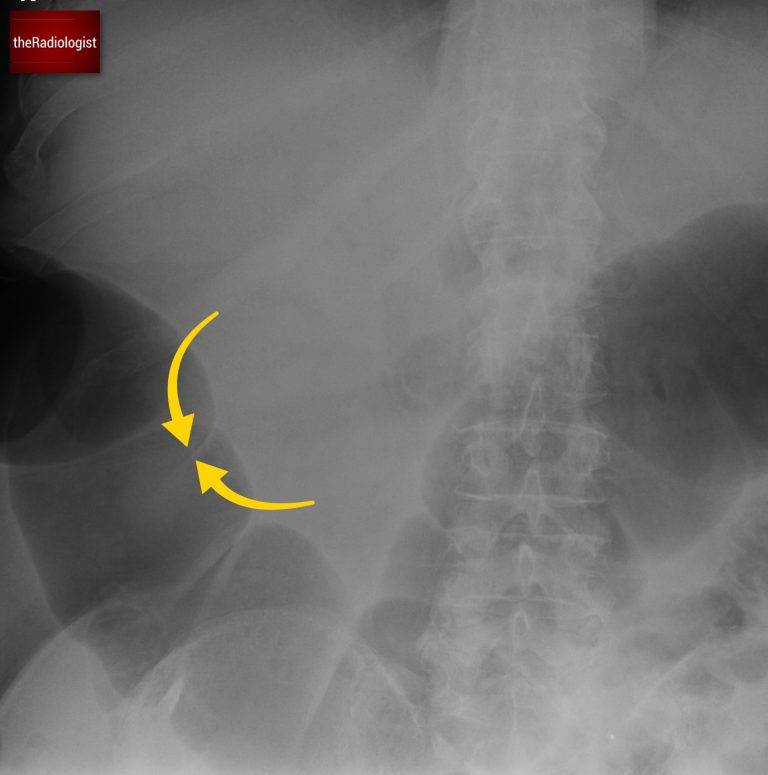

Where you see the bowel helps differentiate between small and large bowel. Dilated small bowel tends to be central, with valvulae conniventes traversing the full width of the bowel. Dilated large bowel lies more peripherally and shows haustra that do not cross the entire wall.

A case of small bowel obstruction. Here we can see indentations called valvulae conniventes which unlike haustrae do traverse the whole bowel wall.